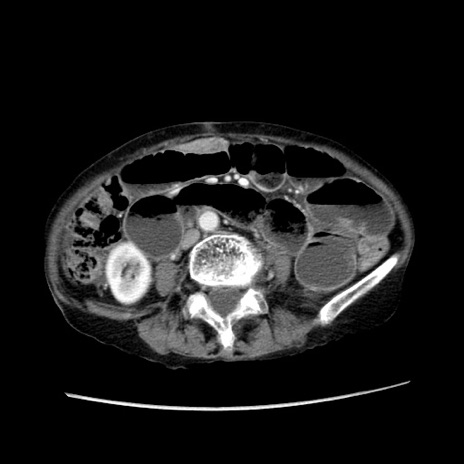

症例25(横断像)

【症例】80歳代女性

【主訴】胸のつかえ感

【現病歴】約9時間前に食後から胸のつかえた感じあり、嘔吐あり、来院。

【既往歴】胃癌(全摘)、胆摘、虫垂炎

【身体所見】心窩部に圧痛あり、反跳痛なし。

【データ】WBC 5700、CRP 0.05